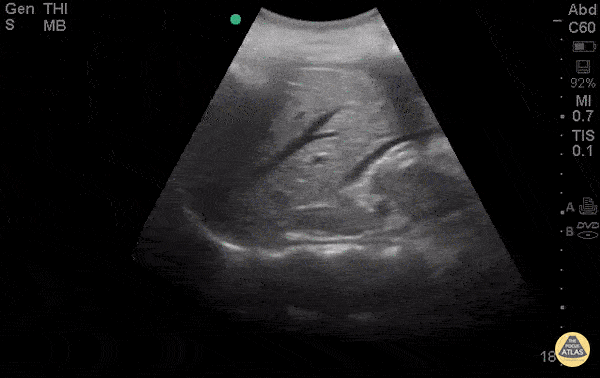

30 y/o F presented to ED for abdominal pain stating she had a recent miscarriage. Now she is having vaginal bleeding for the last 2 weeks. Borderline hypotensive and in severe distress due to pain. Abdomen diffusely tender with guarding. POCUS demonstrated +FAST with blood in the hepatorenal space. Remember to fan all the way to liver tip in FAST scan to fully evaluate for free fluid, it can be subtle and not simply in morrison’s pouch. The patient was rushed to OR by OBGYN for ex-lap based on this scan and was found to have ruptured tubal ectopic pregnancy. Dr. Stacey Frisch - Kings County Emergency Medicine